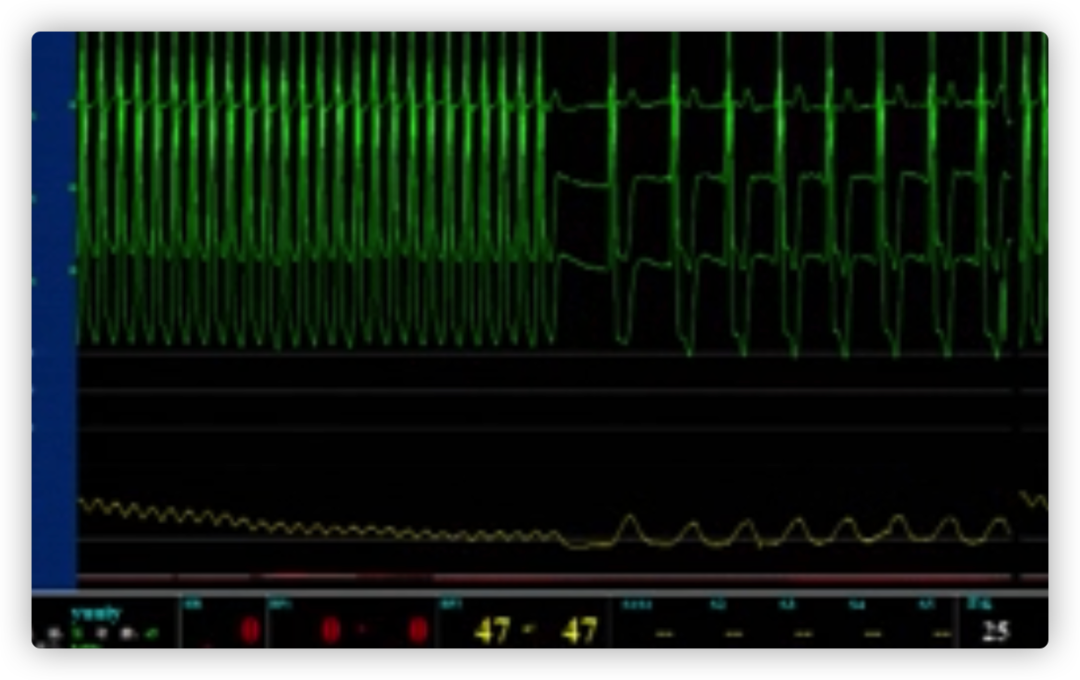

ECG术前

ECG术后即刻

ECG出院时